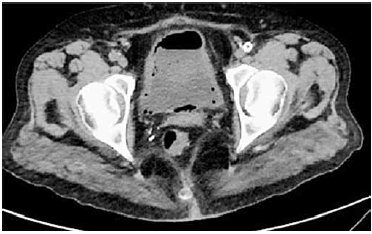

Paciente diabética, portadora de IRC em programa de diálise, apresenta ITU de repetição por Escherichia Coli.

Enunciado 3014210-1

Na CT de bexiga sem contraste, foi encontrado o seguinte diagnóstico: